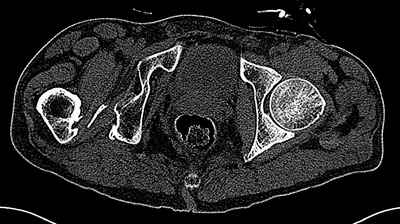

На последнем срезе КТ задний край практически отсутсвует по сравнения со здоровой стороной. Разумеется, что это плоскостное изображение, но головка вывихнулась не только в плоскостную щель захваченную на КТ. Если вы считаете, что удастся установить туда чашку даже низкопрофильную, остается пожелать вам успехов. Но перед этим можно смоделировать установку чашки на скиаграммах КТ.

За пожелание успехов - спасибо, думаю это пригодится, не очень понял про плоскостную щель, специально предоставил срезы на уровне свода - он цел, дефект заднего края ниже, за счет заглубления он будет еще меньше, по данным 3d - должно получиться.

Решение по ВВ придется принимать по месту.... Сумеете "подрыться" и получить хорошее покрытие чашки (+2 винта об-но) - хорошо, если нет -

костная аутопластика из головки.